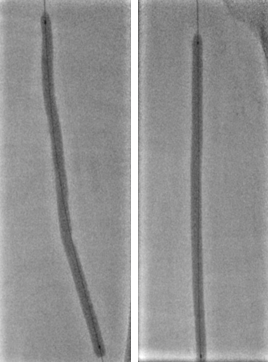

病变类型:严重钙化、长病变

导丝选择:

V-18

Victory™-18,

Asahi Treasure™ 12,

Asahi Astato™ 20,

Asahi Astato™ 30

预扩球囊:

Bantam™ 2x120mm balloon

长期严重钙化

长段严重钙化病变因钙化范围广、质地坚硬,常规扩张治疗易出现血管撕裂、夹层等并发症,且管腔开通效果不佳。定向斑块旋切术凭借 “精准切削、靶向清除” 的核心优势,成为这类复杂病变的优选治疗方案,为临床破解长段钙化难题提供了高效路径。